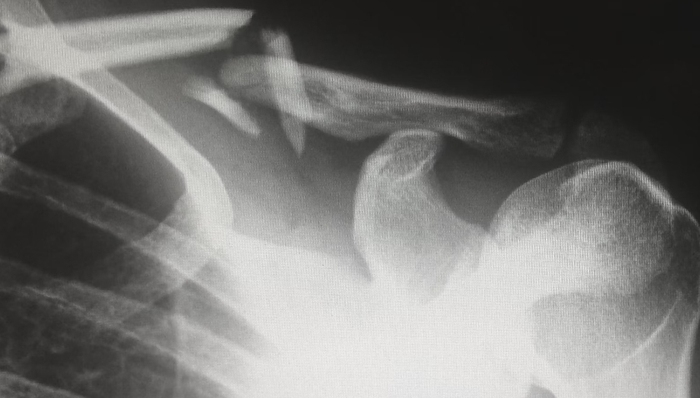

具体来看,此次采购产品包括三类:初次置换人工全髋关节(简称髋关节)、初次置换人工全膝关节(简称膝关节),含增材制造技术(即 3D 打印)类产品。定制化增材制造技术产品可自愿参加。